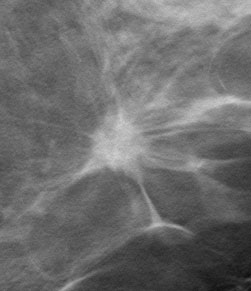

digital mammogram digital tomosynthesis

Invasive Ductal Carcinoma on digital mammogram (above left) and digital tomosynthesis (above right). Digital tomosynthesis shows clear presence of a spiculated mass.